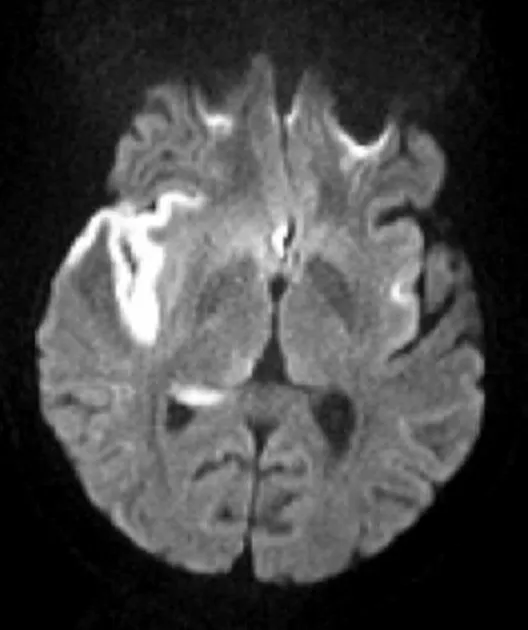

- MRI: Gold standard.

- DWI: Positive within minutes.

- ADC map: Confirms restricted diffusion.

⭐ DWI hyperintensity with corresponding ADC hypointensity signifies restricted diffusion, visible within minutes (<30 min) of acute ischemic stroke onset.